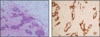

what are the cytological features we are looking for on a microscope to decide if we are delaing with a benign or malignant tissue?

epithelial cells of glandular tissue we are intrested in as this is where breast carcinoma arises

what are aspirates of benign breasts like?

- low/ moderate cellularity

- cohesive groups of cells

- flat sheets of cells

- Bare oval (bipolar) nuclei in background

- cells of uniform size

- uniform chromatin pattern

what does malignant aspiarates look like?

- high cellularity

- crowding/overlapping of cells

- loss of cohesion (resulting is dissociated isngle cells)

- nuclear pleomorphism (larger nuclei and varrying shape)

- hyperchromasia (nuclei look dark - A morphologic finding referring to the presence of darkly stained nuclei due to abundance of DNA on hematoxylin-eosin stained sections. It is suggestive of malignancy.)

- absence of bipolar nuclei